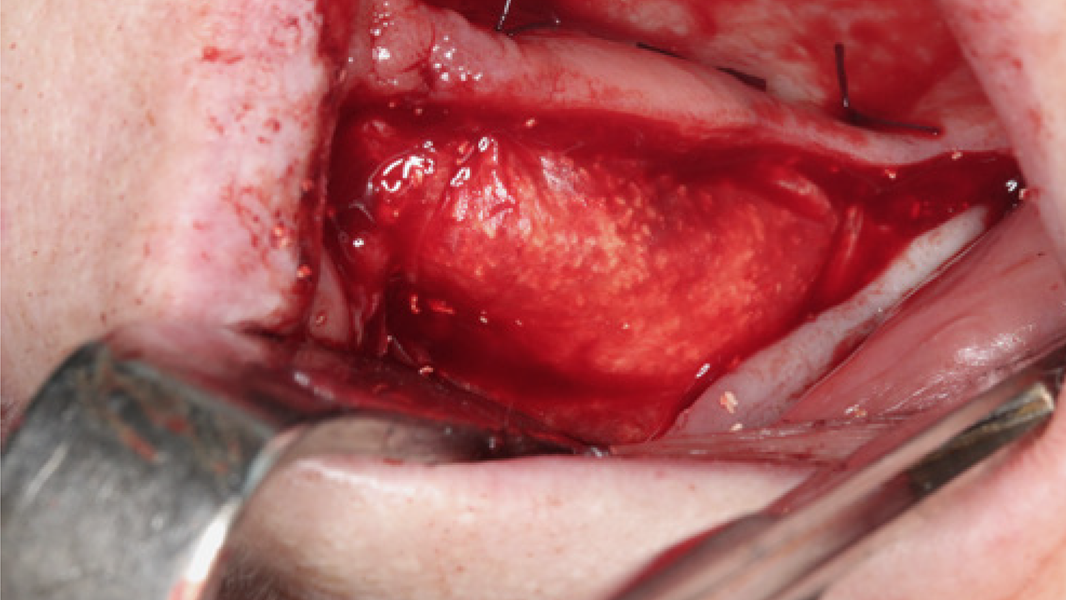

Die rein spongiösen Granulate ermöglichen durch eine zügige Remodellierung einen schnellen Knochenaufbau bei eingegrenzten Defekten, wohingegen das kortiko-spongiöse Material beim Aufbau ausgeprägter knöcherner Defekte für eine längere Volumenstabilität sorgt.

3 Kloss et al. Clin Case Rep. 2020, 8(5):886-893.

15 Data on File. Limited Market Release. Clinical Case Documentation.